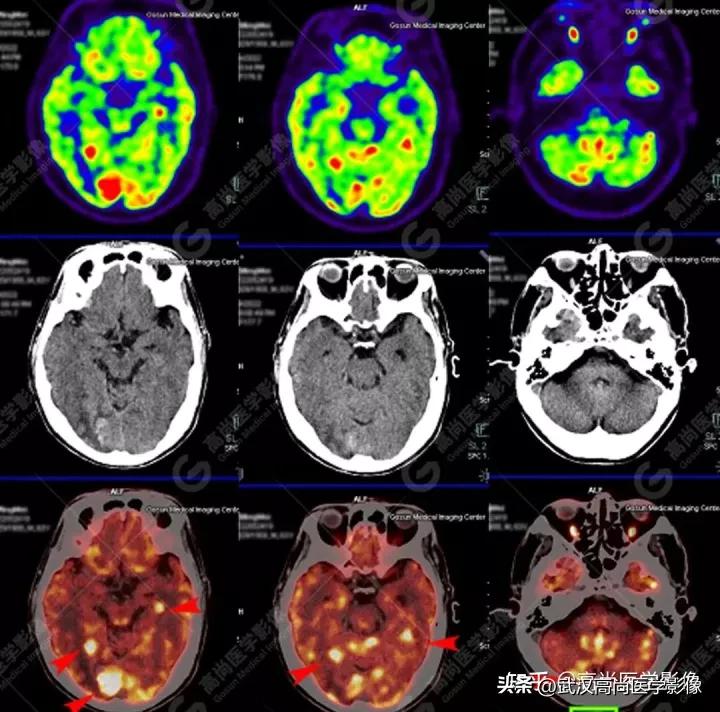

病例一

男性63岁,头痛查体。

脑部影像表现: 脑内多发大小不一的高密度结节,伴瘤周水肿,FDG高摄取,SUVmax20.1。

常见脑转移瘤典型特点: 小肿瘤大水肿,“人小鬼大”。

PET/CT寻找原发灶

PET/CT表现:

全身(右侧颈部、双侧锁骨上区、双侧腋窝、右侧胸小肌后间隙、右侧肺门、纵隔、胰腺周围)多发淋巴结肿大,最大约3.8cm×3.3cm,FDG高摄取,SUVmax6.6。

脾脏一低密度结节,FDG高摄取,SUVmax为3.6。

左侧第2、7肋骨质破坏,合并病理性骨折。

右肺上叶后段一实性结节,大小约1.4cm×1.0cm×1.2cm,边缘分叶征、棘状突起,邻近胸膜稍牵拉,FDG高摄取,SUVmax6.6。

高危结节

PET/CT诊断结论

右肺上叶后段周围型肺癌,伴淋巴结、脑、脾脏、肋骨多发转移。